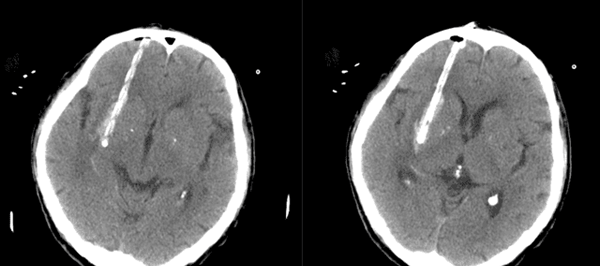

3D打印的導板可以精確直達血腫中心。

△術后不到1天時間拔除頭部引流管,而且可以進食。

△術后3天可以在家人扶持下走路。